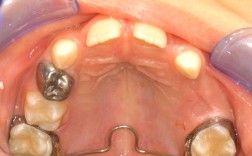

临床技能层面,需将理论知识转化为实操能力,从初诊时的模型分析、X线头影测量(需测量30余项数据)、口内口外照片拍摄,到方案设计(确定拔牙与否、支抗选择、矫治器类型),再到临床操作(托槽粘接、弓丝弯制、橡皮筋牵引),每一步都需精细操作,以“隐形矫正”为例,医生需利用数字化软件设计牙齿移动路径,确保每一步移动符合生物力学原理,同时兼顾患者舒适度;对于“埋伏牙牵引”,需通过外科手术开窗、粘贴附件,结合正畸牵引,耗时数月甚至数年,对医生的耐心和精准度要求极高。